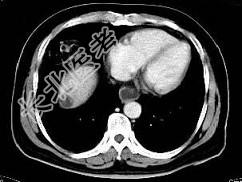

- 单项选择题根据所提供的图像,最可能的诊断是 ( )

A、肝血管瘤

B、局灶性结节增生

C、肝硬化再生结节

D、肝癌

E、肝转移癌